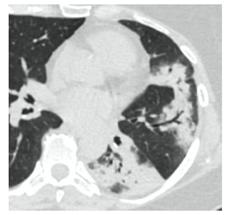

2. Наличие клинических проявлений, указанных в п. 1, в сочетании с характерными изменениями в легких по данным компьютерной томографии (КТ) (см. Приложение 1 настоящих рекомендаций) вне зависимости от результатов однократного лабораторного исследования на наличие РНК SARS-CoV-2 и эпидемиологического анамнеза.

- Изменения при КТ (рентгенографии), типичные для вирусного поражения (объем поражения минимальный или средний; КТ 1-2)

- Изменения в легких при КТ (рентгенографии), типичные для вирусного поражения (объем поражения значительный или субтотальный; КТ 3-4)

- Изменения в легких при КТ (рентгенографии), типичные для вирусного поражения критической степени (объем поражения значительный или субтотальный; КТ 4) или картина ОРДС.

КТ имеет высокую чувствительность в выявлении изменений в легких, характерных для COVID-19. Применение КТ целесообразно для первичной оценки состояния ОГК у пациентов с тяжелыми прогрессирующими формами заболевания, а также для дифференциальной диагностики выявленных изменений и оценки динамики процесса. КТ позволяет выявить характерные изменения в легких у пациентов с COVID-19 еще до появления положительных лабораторных тестов на инфекцию с помощью МАНК. В то же время, КТ выявляет изменения легких у значительного числа пациентов с бессимптомной и легкой формами заболевания, которым не требуется госпитализация. Результаты КТ в этих случаях не влияют на тактику лечения и прогноз заболевания при наличии лабораторного подтверждения COVID-19. Поэтому массовое применение КТ для скрининга асимптомных и легких форм болезни не рекомендуется.